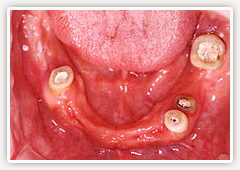

【術前】

下の歯は4本しか残っていません。しかし、人と話をする職業柄、義歯はイヤで今迄過ごしていました。